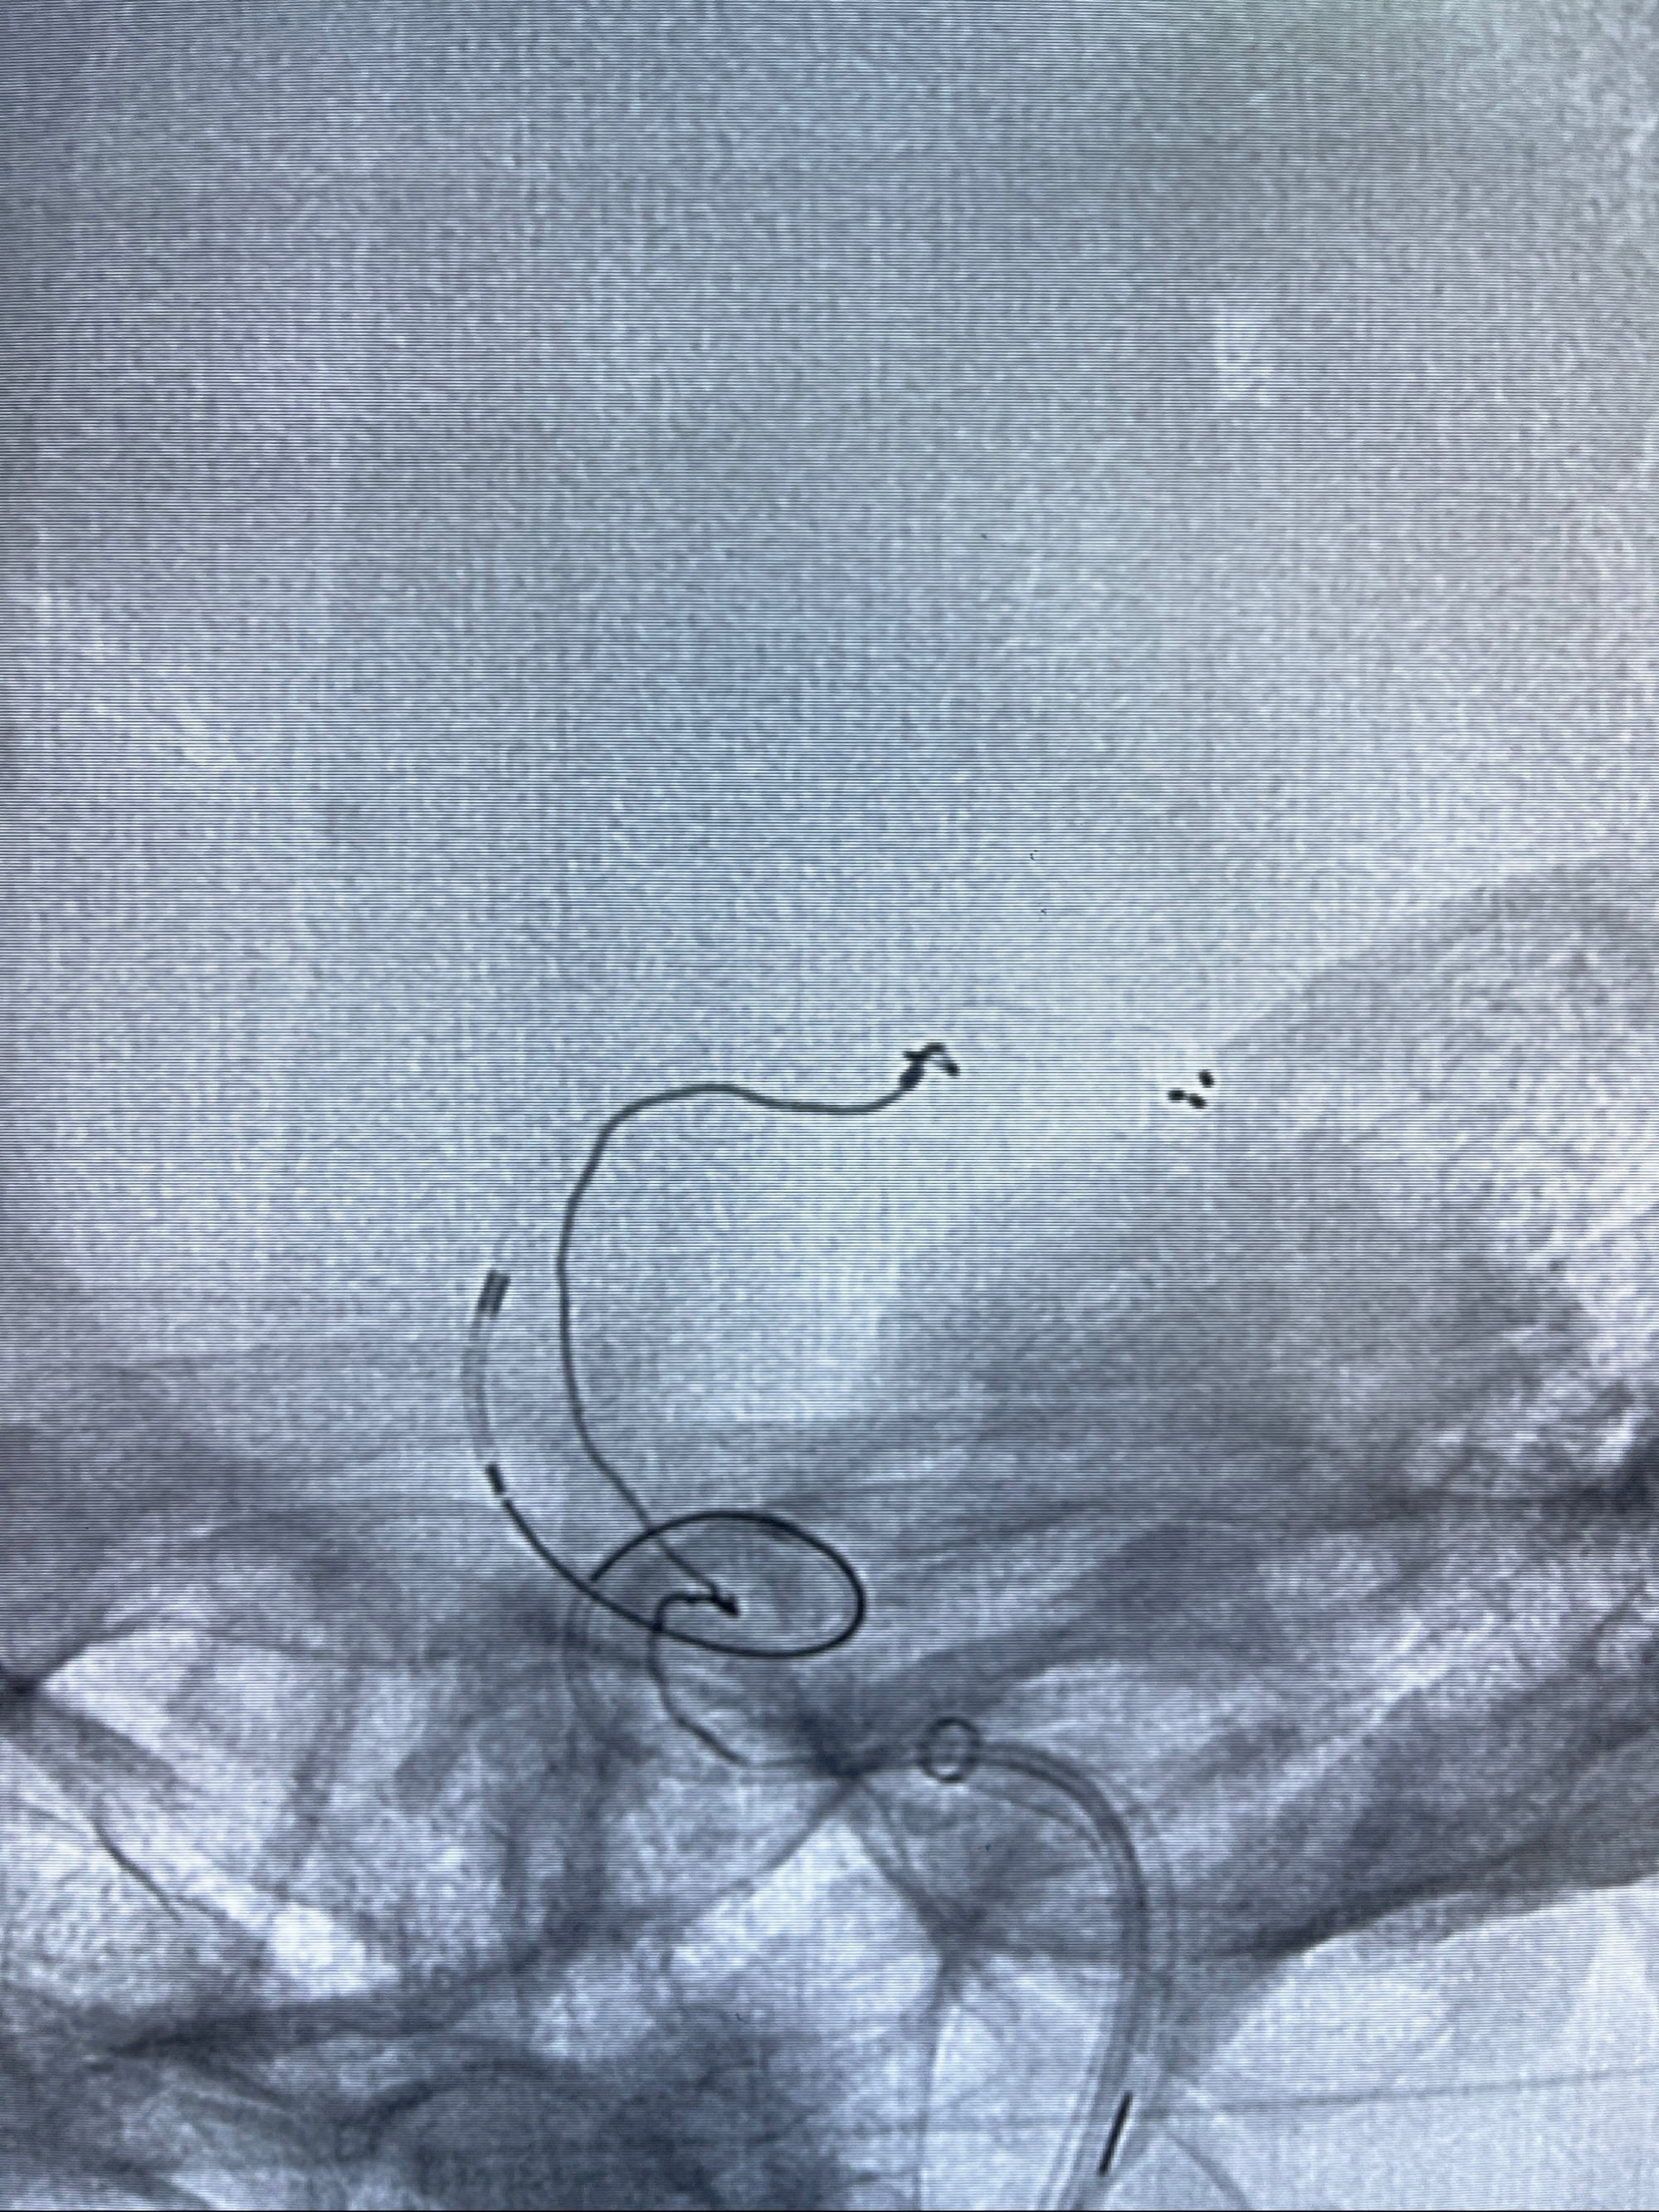

2.外科手术夹闭or介入支架辅助栓塞

麻醉苏醒佳,遵嘱动作

术后即刻CT